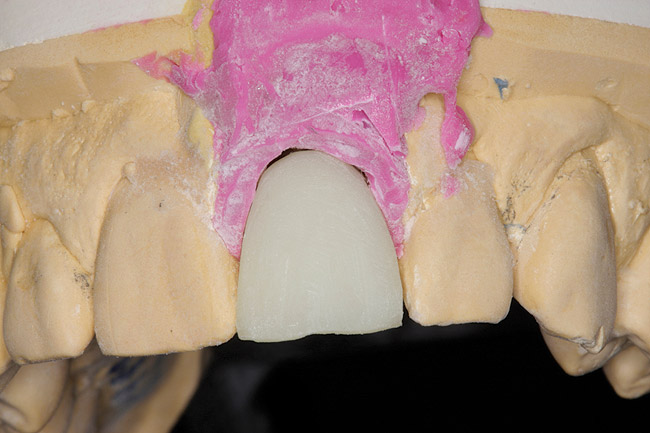

Cast altered so indexed transfer coping can seat with appropriate analog attached.

Figure 2

The restorative dentist can duplicate the contours of the extracted tooth for the new screw-retained provisional following these instructions: First make an index of implant position with a transfer coping. Then, either pour up a working cast or alter the cast used to fabricate the surgical guide. The cast is altered in the area of the implant fixture to allow the indexed transfer coping to seat with the appropriate analog attached (Figure 2).